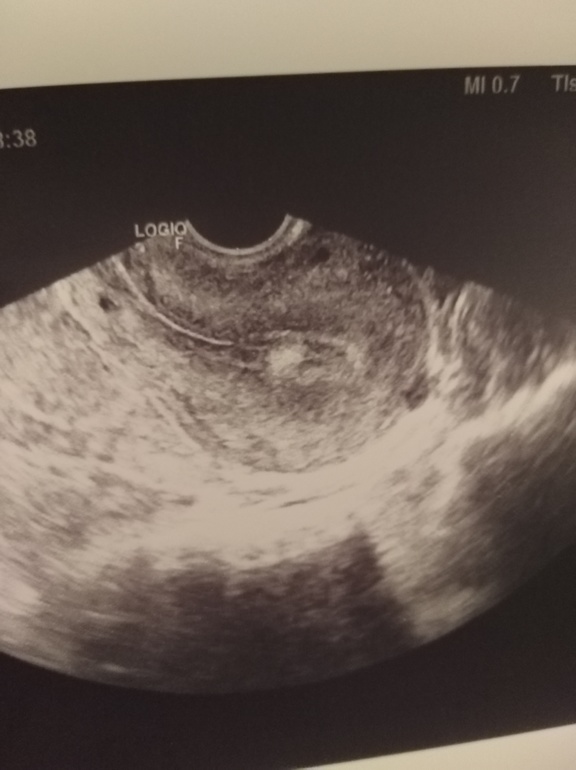

Гинекологические заболеванияДевочки, сижу реву. Всё таки не с проста предыдущий цикл был странный( была задержка три дня и месячные странно шли. Пошла сегодня сделать узи из-за болей похожих на овуляцию, так у меня действительно уже желтое тело и жидкость, эндометрий 9 и это на 9 дц! Обычно овуляция на 16-18 дц. И бонусом нашли полип! 0,8х0,6 размером! 5 месяцев назад на узи ничего не было такого. Только начали планировать после выкидыша и на тебе! И так полно угроз при беремености, так еще и полип! А у нас вчера был ПА, блин, надеюсь не попали((( с полипом то нельзя беременеть(( сказали ждать следующих месячных , если по кожи он будет то операция... за что все это мне. . Сколько сложностей...я в печали

только блин тут видно хорошо что есть какая то белая фигня